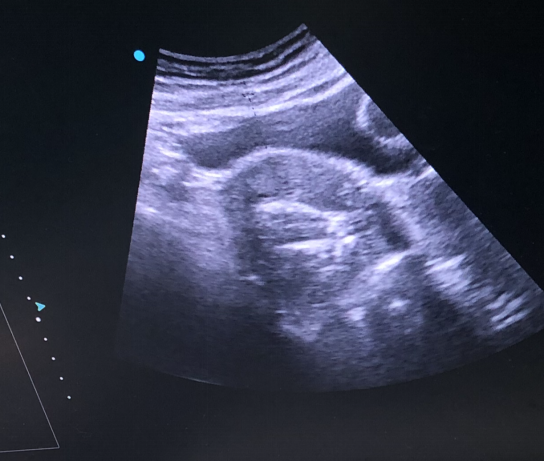

术前:

微波消融后肌瘤病灶内会发生凝固性坏死,即刻超声造影就可以看到病灶内没有造影剂充填。磁共振增强扫描病灶内呈现充盈缺损,增强后呈黑色区域,表示病灶坏死区域。坏死的病灶随时间推移,会逐渐萎缩吸收,子宫体积也会有一定的缩小,从而使痛经、月经量多等临床症状得到缓解和改善。

微波针常用的穿刺路径为B超引导下经皮(经腹壁)或经阴道穿刺,对于有手术史或其他两种路径有困难时还可以选择腹腔镜监视下微波消融。穿刺孔仅有圆珠笔笔芯粗细,腹壁表面无明显疤痕。消融过程会存在一定的疼痛感,微波能量治疗时间大约10分钟左右,可以根据病情选择不同的镇痛或麻醉方式。